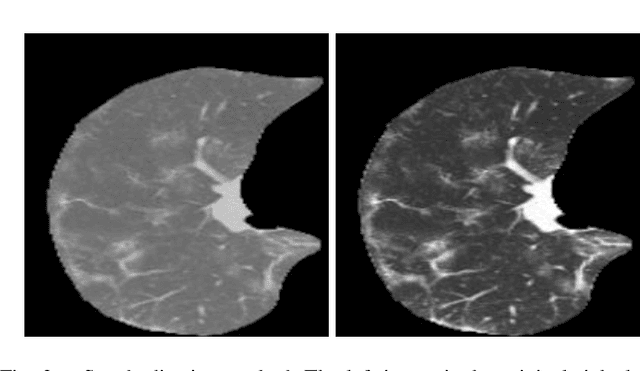

Early detection of COVID-19 is vital to control its spread. Deep learning methods have been presented to detect suggestive signs of COVID-19 from chest CT images. However, due to the novelty of the disease, annotated volumetric data are scarce. Here we propose a method that does not require either large annotated datasets or backpropagation to estimate the filters of a convolutional neural network (CNN). For a few CT images, the user draws markers at representative normal and abnormal regions. The method generates a feature extractor composed of a sequence of convolutional layers, whose kernels are specialized in enhancing regions similar to the marked ones, and the decision layer of our CNN is a support vector machine. As we have no control over the CT image acquisition, we also propose an intensity standardization approach. Our method can achieve mean accuracy and kappa values of $0.97$ and $0.93$, respectively, on a dataset with 117 CT images extracted from different sites, surpassing its counterpart in all scenarios.